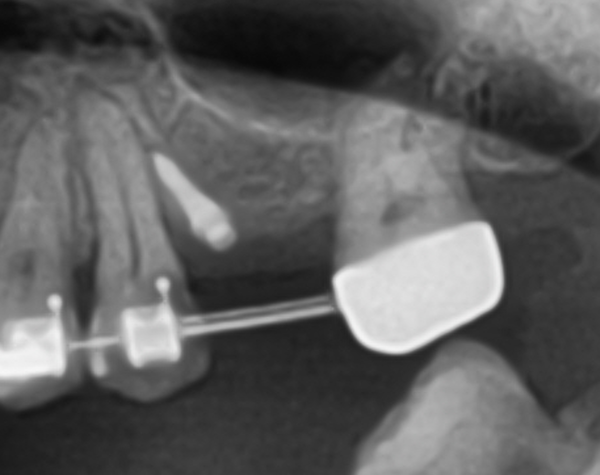

#26 부위에 Magic Guide Pin을 위치시키고 치은의 두께(약 2mm), 잔존골의 높이 (약 4mm)를 계측했다 (그림 5).

#26 치은의 보존을 위해 사선 절개를 시행했고 Magic Guide Pin을 따라 Magic Drill을 사용해 잔존골 2mm를 남기도록 drilling을 시행했다. Magic Sinus Lifter을 사용해 상악동막을 거상한 후 PRF와 골이식을 시행했고 MagiCore를 식립했다(그림 6).